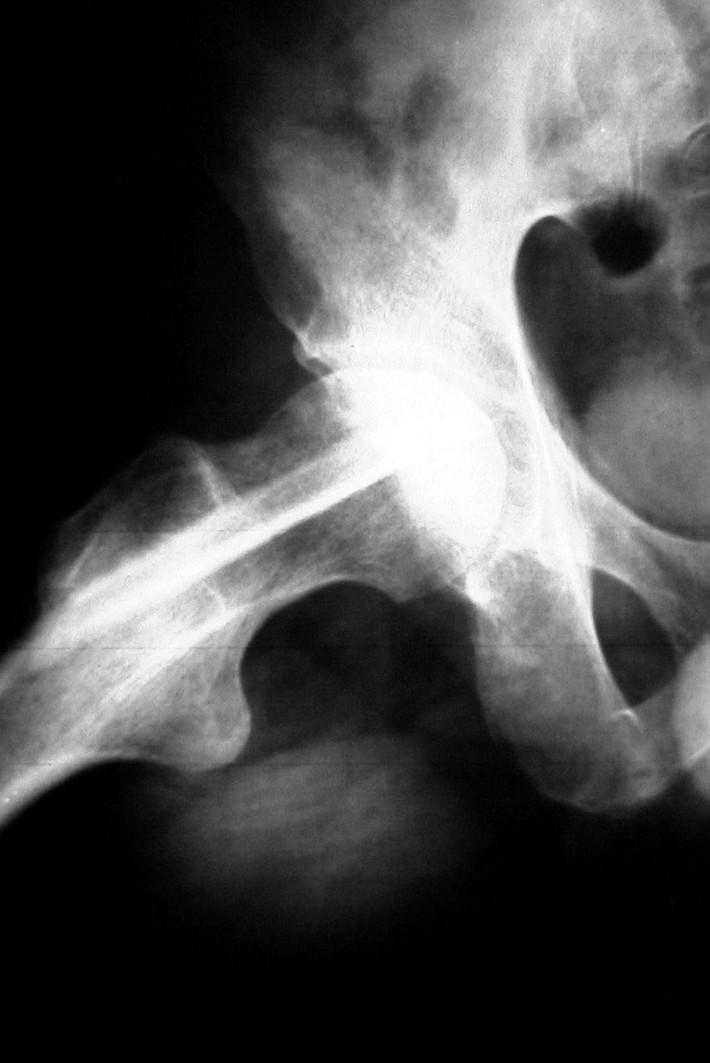

SE APRECIA UNA LINEA DE COLAPSO SUBCONDRAL EL SIGNO DE LA MEDIA LUNARADIOLOGIA NORMAL EL DIAG SE PUEDE REALIZAR POR RESONANCIA MAG

Secuencias Radiológicas

COLAPSO AFECTA LA SUPF SUBCONDRAL PERDIENDO SU MORFOLOGIA NORMAL

LA INCONGRUENCIA ARTICULAR PRODUCE PERDIDA DEL GROSOR DEL CARTILAGO Y CAMBIOS EN EL ACETABULO